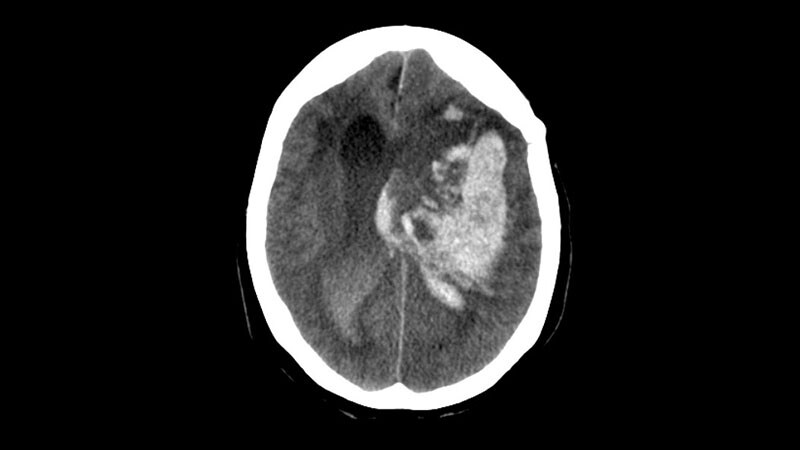

Taking ICH Cases Straight to Endovascular Center May Cause HarmRACECAT trial results suggest the longer travel times to the comprehensive stroke center -- rather than going to a closer

primary stroke center -- could be harmful for patients having a hemorrhagic stroke.